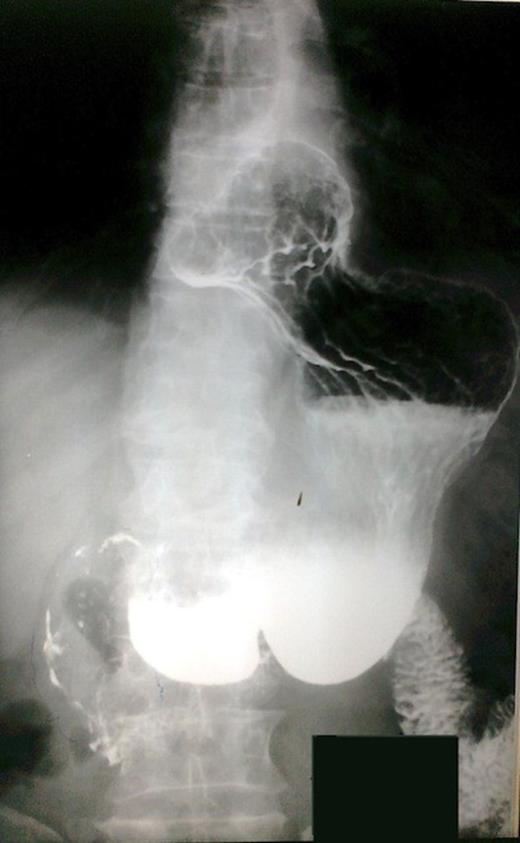

The patient underwent investigation with gastroscopy, where torsion of the bulb of the stomach was found. The insertion of the instrument via the pylorus was not impossible (Figure 1). The upper gastrointestinal series disclosed polypous masses in the bulb and the prepyloric part of the stomach (Figure 2). The computerized tomography (CT) scan was unremarkable. The magnetic resonance (MRI) scan showed an exophytic mass with disturbance of the plication of the intestinal lumen in the area of the pylorus and the duodenum. Also, few small hepatic cysts were found.

Upper gastrointestinal series. Polypous masses in the bulb and the prepyloric part of the stomach